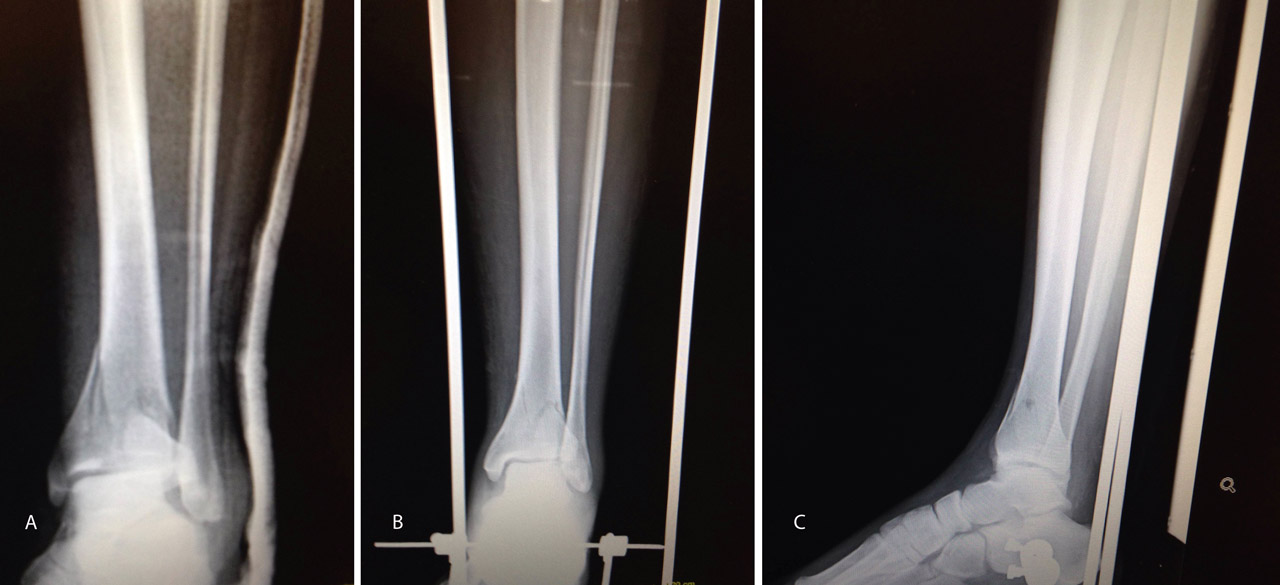

En este caso, es esencial observar las Rx con y sin tracción que nos indican cómo se va a comportar la fractura. Si la fractura es reductible en tracción, es muy probable que podamos realizar una osteosíntesis con restitución completa de la superficie articular. Al realizar la TC, apreciamos la disposición de los fragmentos para marcar una estrategia de reducción bajo control radioscópico y artroscópico, y colocación de los tornillos canulados que fijarán la epífisis distal de la tibia.

Figura 17. Caso 3: fractura tipo C. Radiografías sin tracción y con tracción comprobando la reducción.